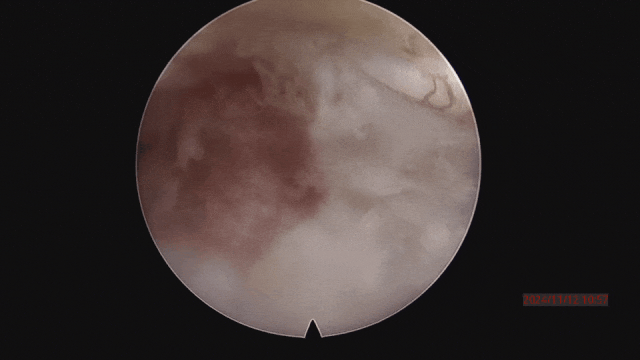

▲取骨块的过程。

▲取骨块后,解除神经压迫。